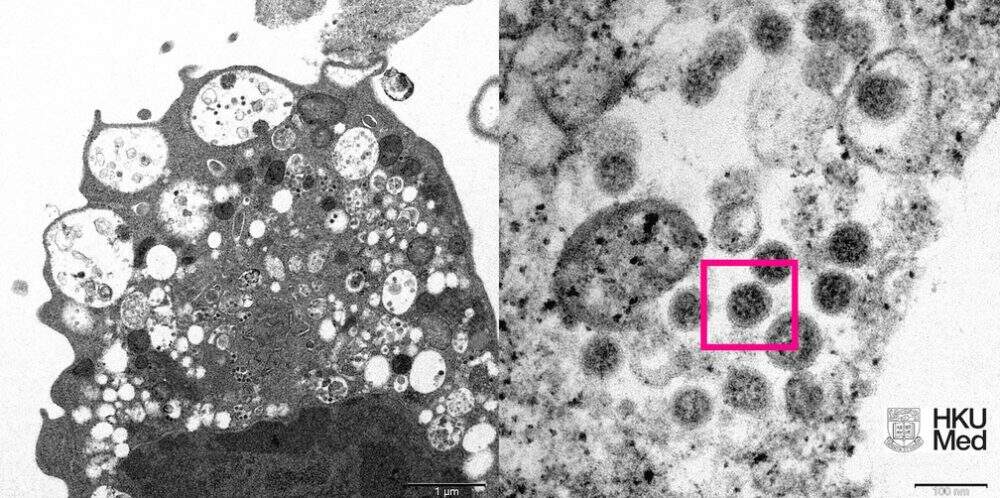

Na imagem da esquerda, explicam os cientistas, é possível ver um recorte “de baixa ampliação” de uma célula de rim de macaco infectada intencionalmente com essa variante do Sars-Cov-2.

Nela, é possível ver que a ômicron provoca danos em nível celular com vesículas – essas pequenas bolhas – cheias de pequenas partículas virais (identificadas pela cor preta).

Já na imagem da direita, a micrografia eletrônica tem alta ampliação desta mesma célula, mas mostrando as partículas virais mais de perto (dentro deste quadrado cor de rosa).

Neste registro, é possível inclusive ver a coroa do coronavírus (formada pela proteína S) ao redor da partícula viral.

A imagem foi produzida pelos professores John Nicholls, Malik Peiris e Tam Wah-Ching da Universidade de Hong Kong.